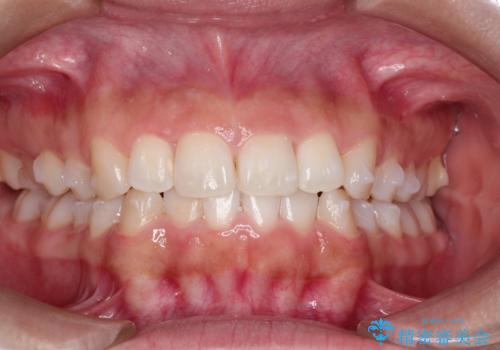

- 初診時には前歯部に捻転や叢生、臼歯部にも一部叢生が見られる状態でした。

インビザラインでの治療を計画し、行っていきました。

インビザライン治療により、捻転を含む歯列もしっかりと改善しています。

基本的な不正咬合部分は初回の30枚のマウスピースでほぼ改善しており、リファインメントでは前歯部の細かな調整など、患者様の要望を取り入れる形でシミュレーションをセットアップし、満足の行く結果に仕上がりました。